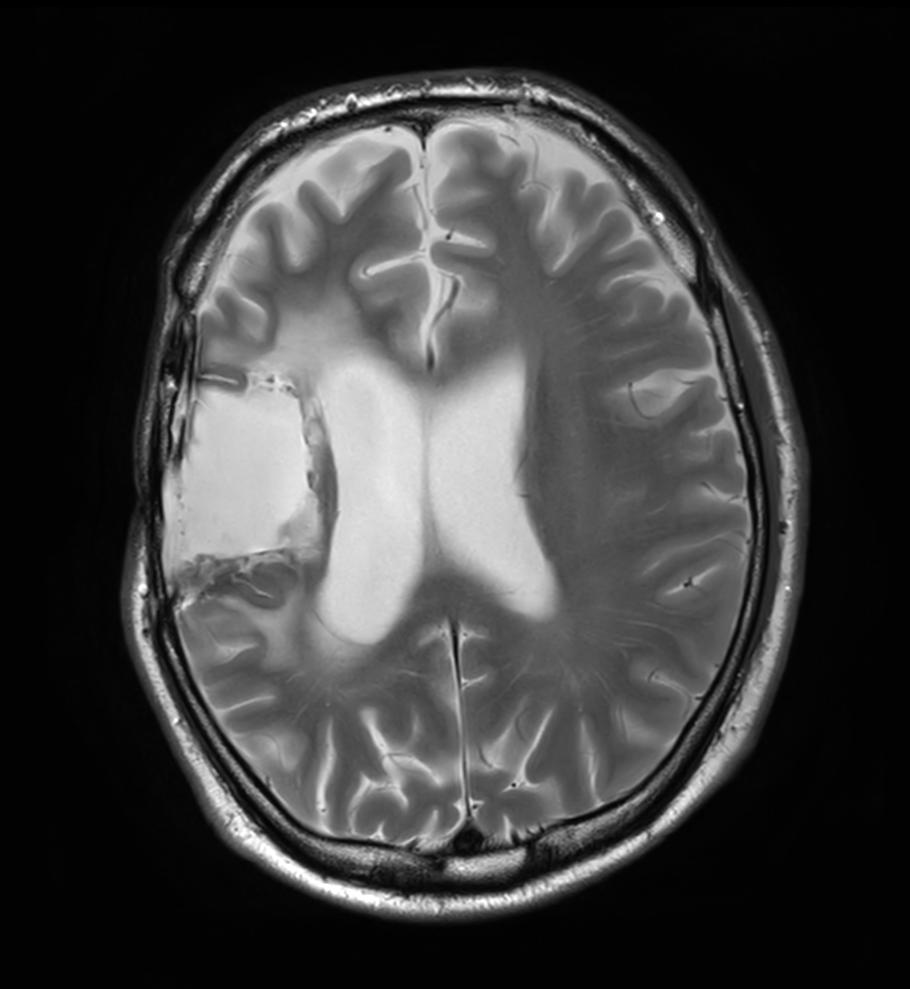

Axial T2w TSE

Axial DTI (ADC)

3D T1w TFE - Axial reformat

3D T1w TFE - Axial reformat (with gado)

3D T1w TFE - Axial reformat (high res, with gado)